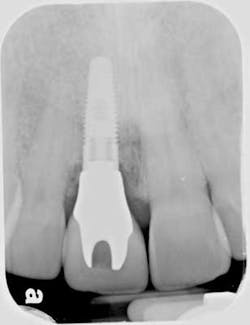

Of all the problems that can occur with implant placement in the anterior, not controlling the zenith of gingival contour may be the most troublesome when it comes to anterior esthetics. Gingival zenith or height of gingival contour is defined as the apex of the gingival height. There are many ways to lose several millimeters of peri-implant mucosa, and it has been shown that even a 1 mm apical displacement of peri-implant mucosa may result in insurmountable limitations in anterior implant esthetics. Things such as deep implant placement, buccal resorption, and relative tooth eruption are just some of the things that can cause this loss of tissue.

When planning surgery with my periodontist, we both decide where we want the zenith to be esthetically, and then plan implant placement 3 mm apical and 2 mm palatal to this location. Biologically speaking, this location will allow us to preserve the zenith from a placement standpoint. Keep in mind that we need to have the tissue healthy and under control prior to starting any procedure.